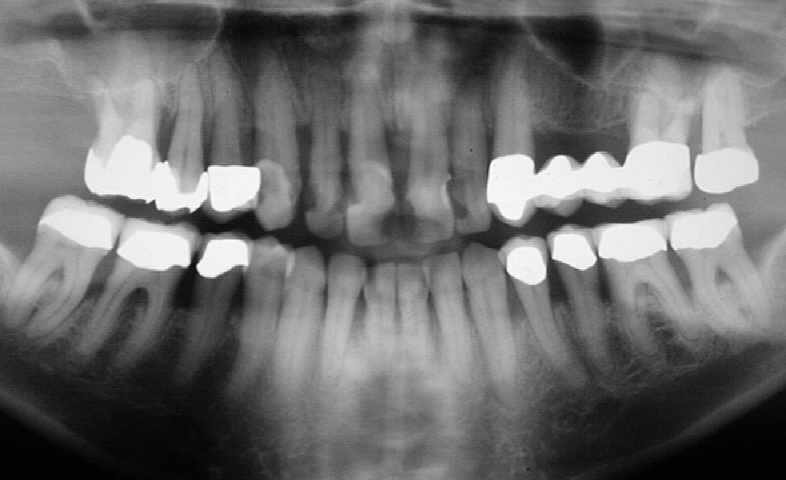

Die ursprünglich als therapieresistent eingestufte und ausgesprochen progredient verlaufende Parodontitis ist jetzt seit mehr als 2  Jahren bis auf den jetzt augmentierten Bereich nicht wieder exazerbiert. Und auch in diesem Bereich ist sie jetzt mehr als 1 1/2 Jahre ausgeheilt. Dies ist ein in mehrerer Hinsicht ausgesprochen interessanter und lehrreicher Fall.

Ausgangsbefund vor Par-Behandlung im August 1999      (Klick!)

Auffällig ist, dass sich der Erfolg der Maßnahme trotz der ausgesprochen ungünstigen Voraussetzungen eher in Zentimetern als in Millimetern messen lässt, wobei die Sondierungstiefen dem Röntgenbefund entsprechen. Dies, obwohl es sich eher um eine Verzweiflungstat unsererseits gehandelt hat, keine Membran benutzt wurde, lediglich Cerasorb ohne zusätzlichen Eigenknochen eingebracht wurde, es zur zweimaligen Nahtdehiszenz mit anschließender sekundärer Wundheilung kam, man die Caerasorb-Kügelchen längere Zeit klinisch freiliegend beobachten konnte.

Dieser Fall, der eindeutig Lindhes Kriterien entspricht, die zu dieser Meinungsänderung geführt haben, kann jedoch trotz seines ursprünglich sehr dramatischen Verlaufs nach dieser langen Periode des Sistierens jeglicher Parodontitissymptomatik in unseren Augen als ausgeheilt betrachtet werden. Wir sehen eigentlich nicht, warum diese Versorgung nicht zumindest die nächsten 10 Jahre ohne weiteren unphysiologischen Knochenverlust überdauern sollte. Ein anderer Verlauf würde uns aufgrund unserer Erfahrung bei vor langer Zeit sanierten Fällen ausgesprochen überraschen. Dies um so mehr, als das Problem im Bereich 14-15-16 offensichtlich beseitigt ist.